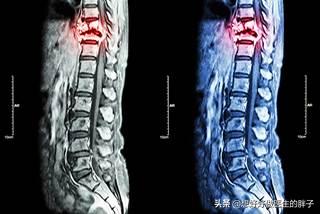

骨転移はどのような痛みに注意すべきですか?骨転移は悪性腫瘍の末期によく見られる症状で、体の他の部位にある原発腫瘍が血液やリンパ液の経路を通って骨に転移し、骨転移を形成することを指します。骨転移は、正常な骨組織が破壊され、腫瘍組織に置き換わっていることを示す。骨転移は病変の特異性により、溶骨型、造骨型、混合型の3つに分類される。骨転移の好発部位は中軸骨(脊椎、骨盤)、肋骨、下部骨幹部で、特に中軸骨が最も多く、これはこの部位の血液供給の特徴と関係しています。下の円のように骨転移が多発し、脊椎の状態が悪い。

骨転移で起こる症状にはどのようなものがありますか?最初の症状は痛みです。骨転移を起こした部位は骨が破壊されるために痛みを感じますが、最初ははっきりした症状がなかったり、断続的な痛みだったりしますが、腫瘍が正常な骨をどんどん破壊して徐々に悪くなっていくため、転移部位の痛みも徐々に悪くなっていきます。臨床的には、体のある部分の骨の痛みで、悪性腫瘍の骨転移という症例に出くわすことがあります。以前、ある症例に出会ったのですが、40歳で、肩が痛く、五十肩かと思い、薬用オイルを数日揉んでも改善が見られず、ますます痛みが強くなったので、病院で検査をしたところ、MRIを撮ったところ、肩甲骨が(腫瘍の)かけらに食べられており、骨転移を考え、胸部CTを撮ったところ、右肺に結節があり、生検をして病理検査をしたところ、肺がんの骨転移でした。その内容は以下の通りである。

骨転移部位では、正常な骨組織が破壊され腫瘍組織に置き換わり、腫瘍細胞は常に増殖しているため、多くの骨転移部位で軟部組織の腫瘤影が見られ、腫瘤が表在する部位であれば触知することができる。また、腫瘍組織による正常な骨組織の侵食は、正常な骨構造の破壊と脆弱化につながるため、正常な外力下でも骨折が生じることがあり、病的骨折と呼ばれます(下図)。脊椎への転移は、疼痛や病的骨折に加えて、脊髄神経根の圧迫を伴い、感覚障害、筋力低下、場合によっては高カルシウム血症などの症状を呈することもあります。

骨転移の磁気共鳴画像法

胸椎に発生した骨転移性癌を示す。